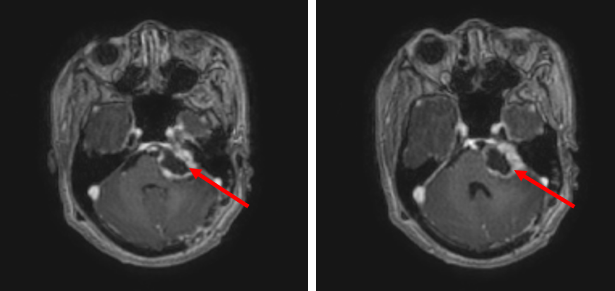

Trước phẫu thuật:

Hình 1: Vị trí góc cầu tiểu não trái có khối tổn thương, kích thước 28x29x32mm, đồng tín hiệu trên T2W, ngấm thuốc không đồng nhất.